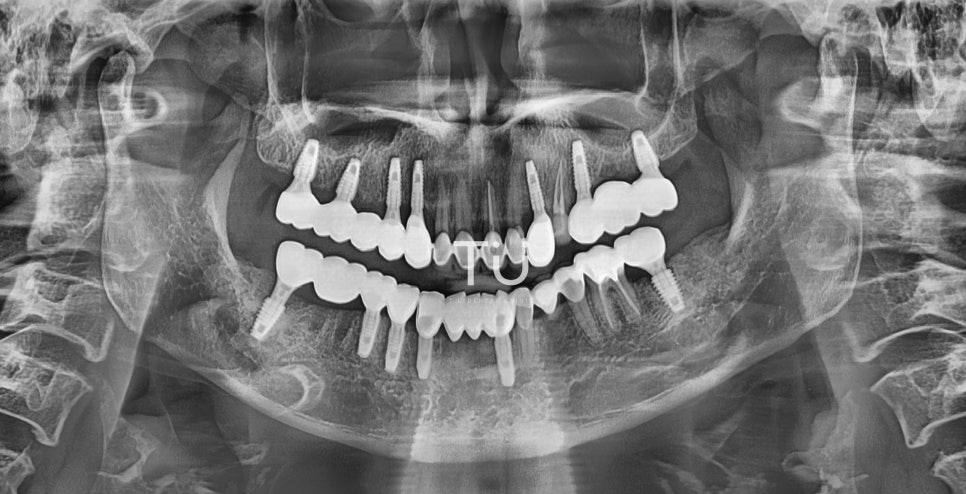

(보철완료 후 최종)

임플란트의 머리 부분인 크라운(crown)까지

식립이 완료된 최종 After 입니다!

총 13개의 임플란트를 식립하였으며,

연결치아 6개로 총 치아개수 19개가 완성되었습니다.

힘든 수술이셨을텐데, 환자분의 협조도가 높아

더더욱 수월하게 마칠 수 있었답니다.

이전에는 식사시간이 너무 고통스러웠는데,

이제는 편안하게 식사를 할 수 있어

마음이 놓인다고 무척 좋아하셨어요 ☺